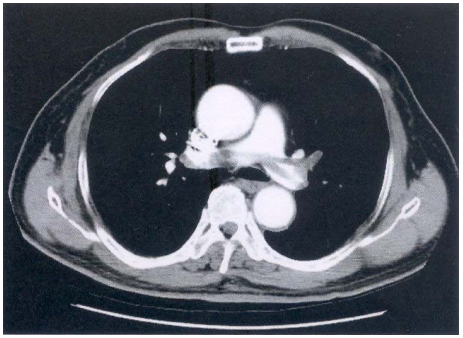

76 76 歲男性主訴胸悶和呼吸不順暢,注射對比劑後 CT 影像如附圖,則最可能的診斷為下列何者? (A)肺主動脈瘤 (B)肺動脈栓塞 (C)上行主動脈瘤 (D)上腔靜脈狹窄